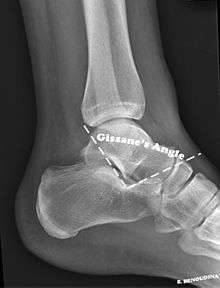

The Angle of Gissane, or "Critical Angle", is the angle formed by the downward and upward slopes of the calcaneal superior surface. On a lateral radiograph, an angle of Gissane of > 130° suggests fracture of the posterior subtalar joint surface. Bohler's angle, or the "Tuber Angle", is another normal anatomic landmark seen in lateral radiographs. It is formed by the intersection of 1) a line from the highest point of the posterior articular facet to the highest point of the posterior tuberosity, and 2) a line from the former to the highest point on the anterior articular facet. An angle < 20° suggests a depression of posterior facet and possible calcaneal fracture.